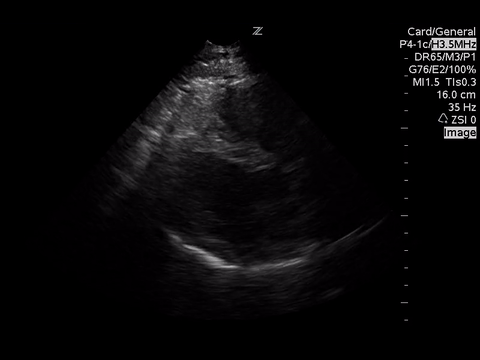

Below are three cardiac views. Think of what you would be looking for given the clinical scenario.

Mostly with intermediate point of care echocardiography, in this patient, we would be looking for gross LV function using the “eyeball” method, presence of a pericardial effusion and rough RV:LV size.

In these images, we can estimate that the LV function is grossly normal and there is no pericardial effusion. Unfortunately, due to quality, we are unable to comment on the RV:LV size ratio. However, we would be looking for a RV:LV ratio of 0.6:1 as normal with a ratio of 1:1 as severe RV dilation.